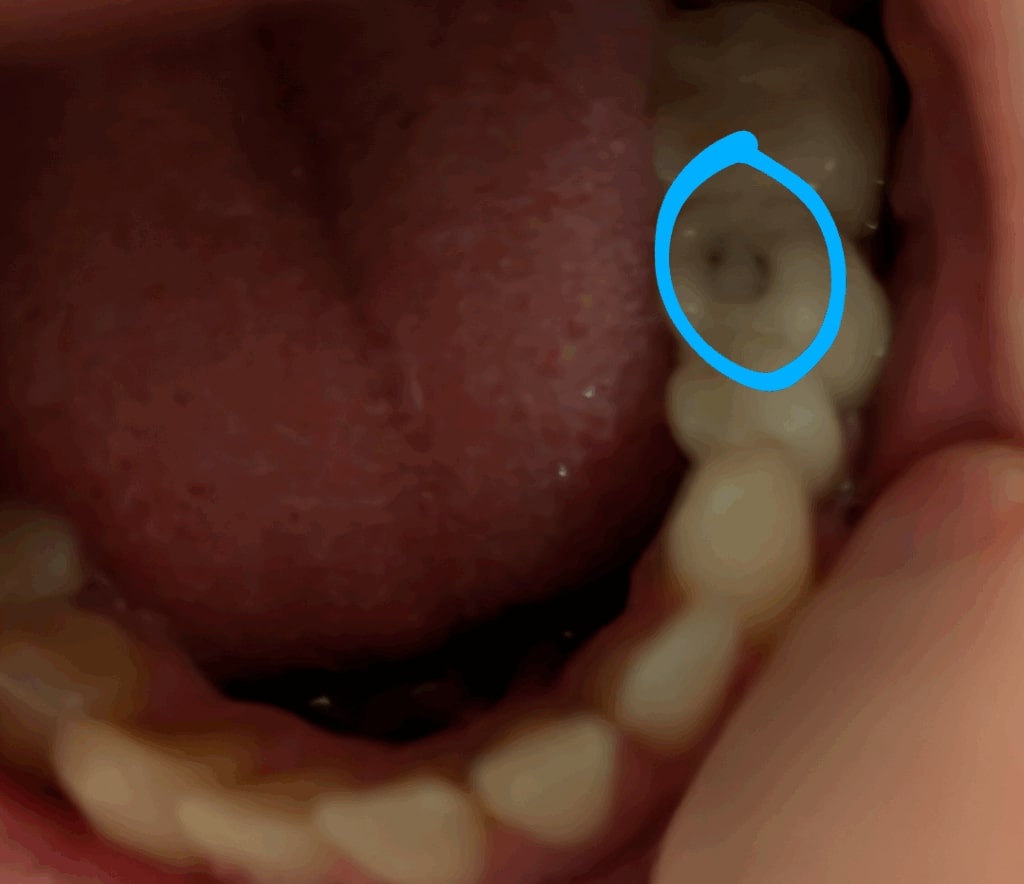

Vierte Entzündung nach Aufplatzung der Versiegelung von Dr. Schilderoth

Nur paar Wochen später nachdem Dr. Schilderoth meinen Zahn (35) öffnete und versiegelte, platzte die Versiegelung am Zahn auf! Die Versiegelung war nur paar Wochen alt! Ich zeigte Dr. Schilderoth die Aufplatzung und er sagte, dass sie bedenkenlos sei und hat mich mit der aufgeplatzten Stelle wieder entlassen.

So hat er mich entlassen und die Behandlung als abgeschlossen erklärt:

Nur wenig später begann es plötzlich bei der aufgeplatzten Stelle zu brennen, und das immer wenn Flüssigkeit auf die aufgeplatzte Stelle kam. Das Brennen war bis im Zahninneren vom Zahn (35) zu spüren, sodass wohl durch die Aufplatzung ein Riss im Zahn entstanden ist und mein umliegendes Gewebe völlig entzündet hat.

Dr. Schilderoth hat also nicht nur die Entzündung von drei gesunden Zähnen durch seine Beschleifung verursacht, sondern auch noch eine vierte Entzündung, weil er meinte, meine Aufplatzung sei bedenkenlos und müsse nicht repariert werden. Ich denke, ein seriöser Zahnarzt hätte mich mit der Aufplatzung nicht entlassen, egal ob bedenkenlos oder nicht. Vor allem nicht nach den vielen entstandenen Entzündungen und Problemen durch seine Behandlungen, worunter man ja ziemlich leidet.

Dr. Schilderoth hat eine Zahnfistel nicht erkannt, obwohl ich ihn die Stelle der Zahnfistel mehrmals gezeigt hatte. Obwohl der Zahn eine Zahnfistel hat, hat Schilderoth den Zahn einfach überkront, was laut dem neuen Zahnarzt ein großer Fehler war.